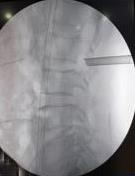

• 单侧双通道内镜与经皮椎间孔镜技术治疗极外侧型腰椎间盘突出症的临床疗效对比

摘要:目的 比较单侧双通道内镜(UBE)与经皮椎间孔镜下髓核摘除术(PTED)治疗极外侧型腰椎间盘突出症(FLLDH)的临床疗效。方法 回顾性分析2021年3月-2023年3月于该院进行治疗的FLLDH患者42例,根据手术方法不同,将患者分为UBE组(18例)和PTED组(24例)。记录并比较两组患者手术时间、术中透视次数、住院时间和围手术期并发症等指标。采用疼痛视觉模拟法(VAS)评估疼痛程度,Oswestry功能障碍指数(ODI)评估功能障碍情况,Macnab评分标准评估临床疗效。结果 UBE组手术时间为(95.56±20.94)min,较PTED组的(78.25±17.23)min长,术中出血量为(69.17±8.95)mL,较PTED组的(23.96±5.89)mL多,差异均有统计学意义(P < 0.05)。UBE组住院时间为(5.67±1.28)d,与PTED组的(5.33±1.05)d比较,差异无统计学意义(P > 0.05)。UBE组术中透视次数为(3.00±0.77)次,明显少于PTED组的(7.42±0.93)次,差异有统计学意义(P < 0.05)。两组患者术后VAS评分和ODI较术前明显降低,差异均有统计学意义(P < 0.05)。术后3 d,UBE组腿痛VAS评分为(3.28±0.58)分及ODI为(41.17±4.30)%,明显低于PTED组的(4.13±0.74)分及(45.50±3.91)%,差异均有统计学意义(P < 0.05),但两组患者术后3个月和1年的VAS评分及ODI比较,差异均无统计学意义(P > 0.05)。两组患者优良率比较,差异无统计学意义(88.9%和87.5%,P = 0.563)。PTED组围手术期出现神经损伤2例,UBE组无神经损伤出现,两组均无感染、复发和大出血等严重并发症发生。结论 PTED与UBE两种手术方式治疗FLLDH均安全和有效。但UBE术中透视次数少,镜下视野更加清晰,神经损伤风险更小。